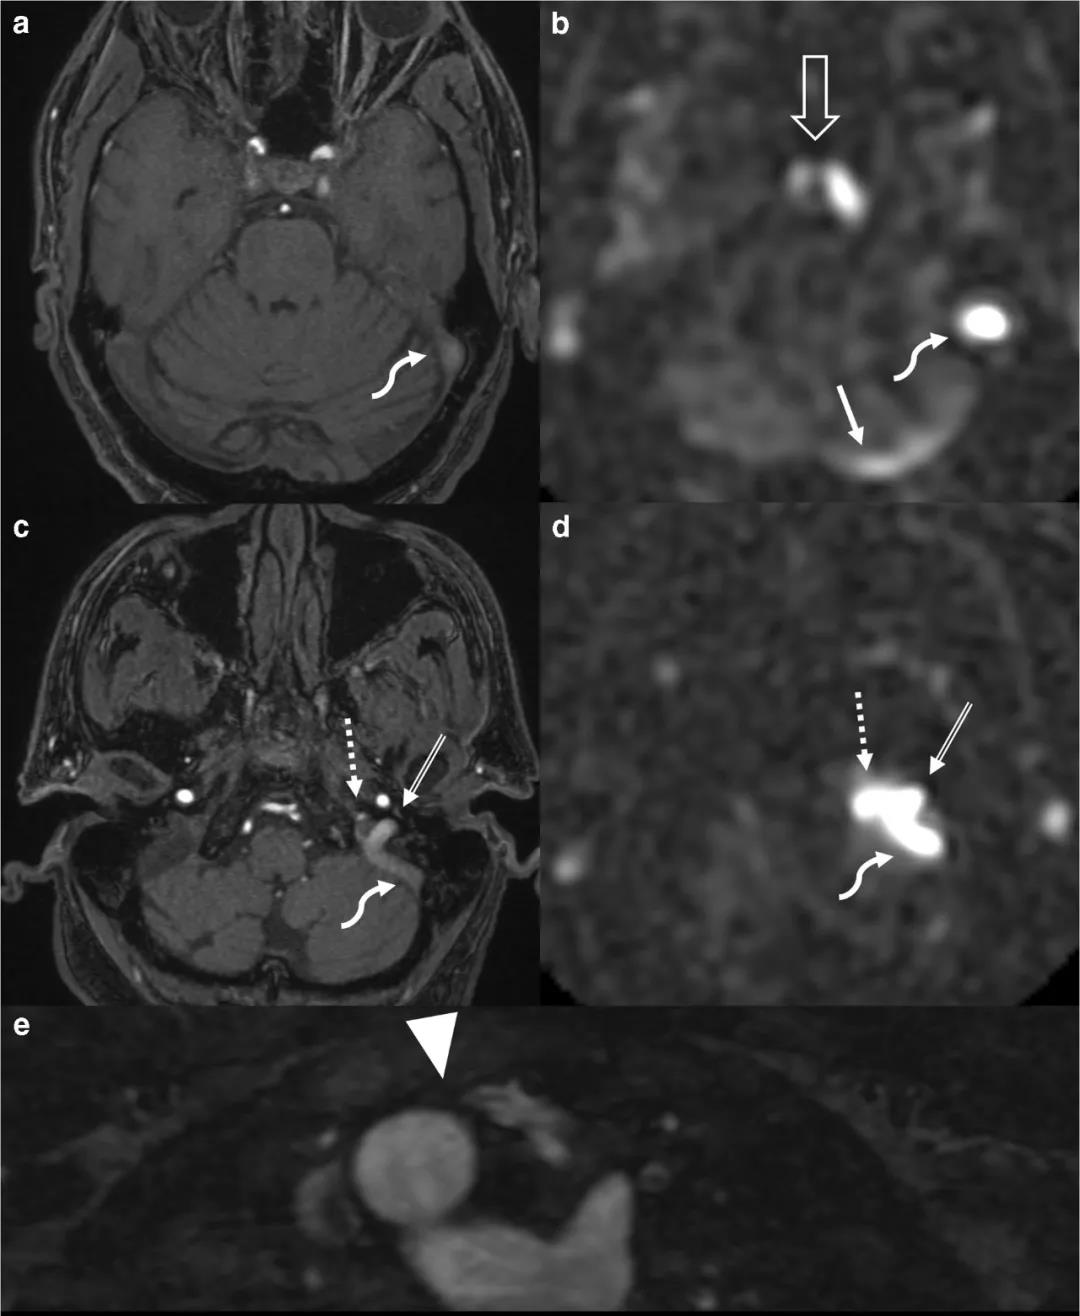

69岁,男性,因头晕被送到急诊室。MRI/MRA排除了血管病因(图1)。颈静脉球、乙状窦和岩下窦 TOF MRA和ASL上可见高信号(图1a-d)。横窦、海绵窦和海绵间窦ASL也显示高信号,在MRA上没有明显的异常信号。颈部增强MRA显示右侧主动脉弓和左侧迷走锁骨下动脉,在胸骨处可见主动脉压迫了左头臂静脉(图1e)。

图1 MRI。在1.5T MRI,平扫3D TOF MRA(a,c) 和3D伪连续ASL(b,d)均显示左乙状窦(曲箭头)、岩下窦(虚线箭头)和颈静脉球(双线箭头)高信号。ASL(b)在左侧横窦(直实心箭头)和双侧海绵窦及海绵间窦(开放箭头)也显示高信号。增强MRA(e)显示右侧主动脉弓,左锁骨下动脉异常,左头臂静脉(箭头)在主动脉和胸骨之间通过时闭塞